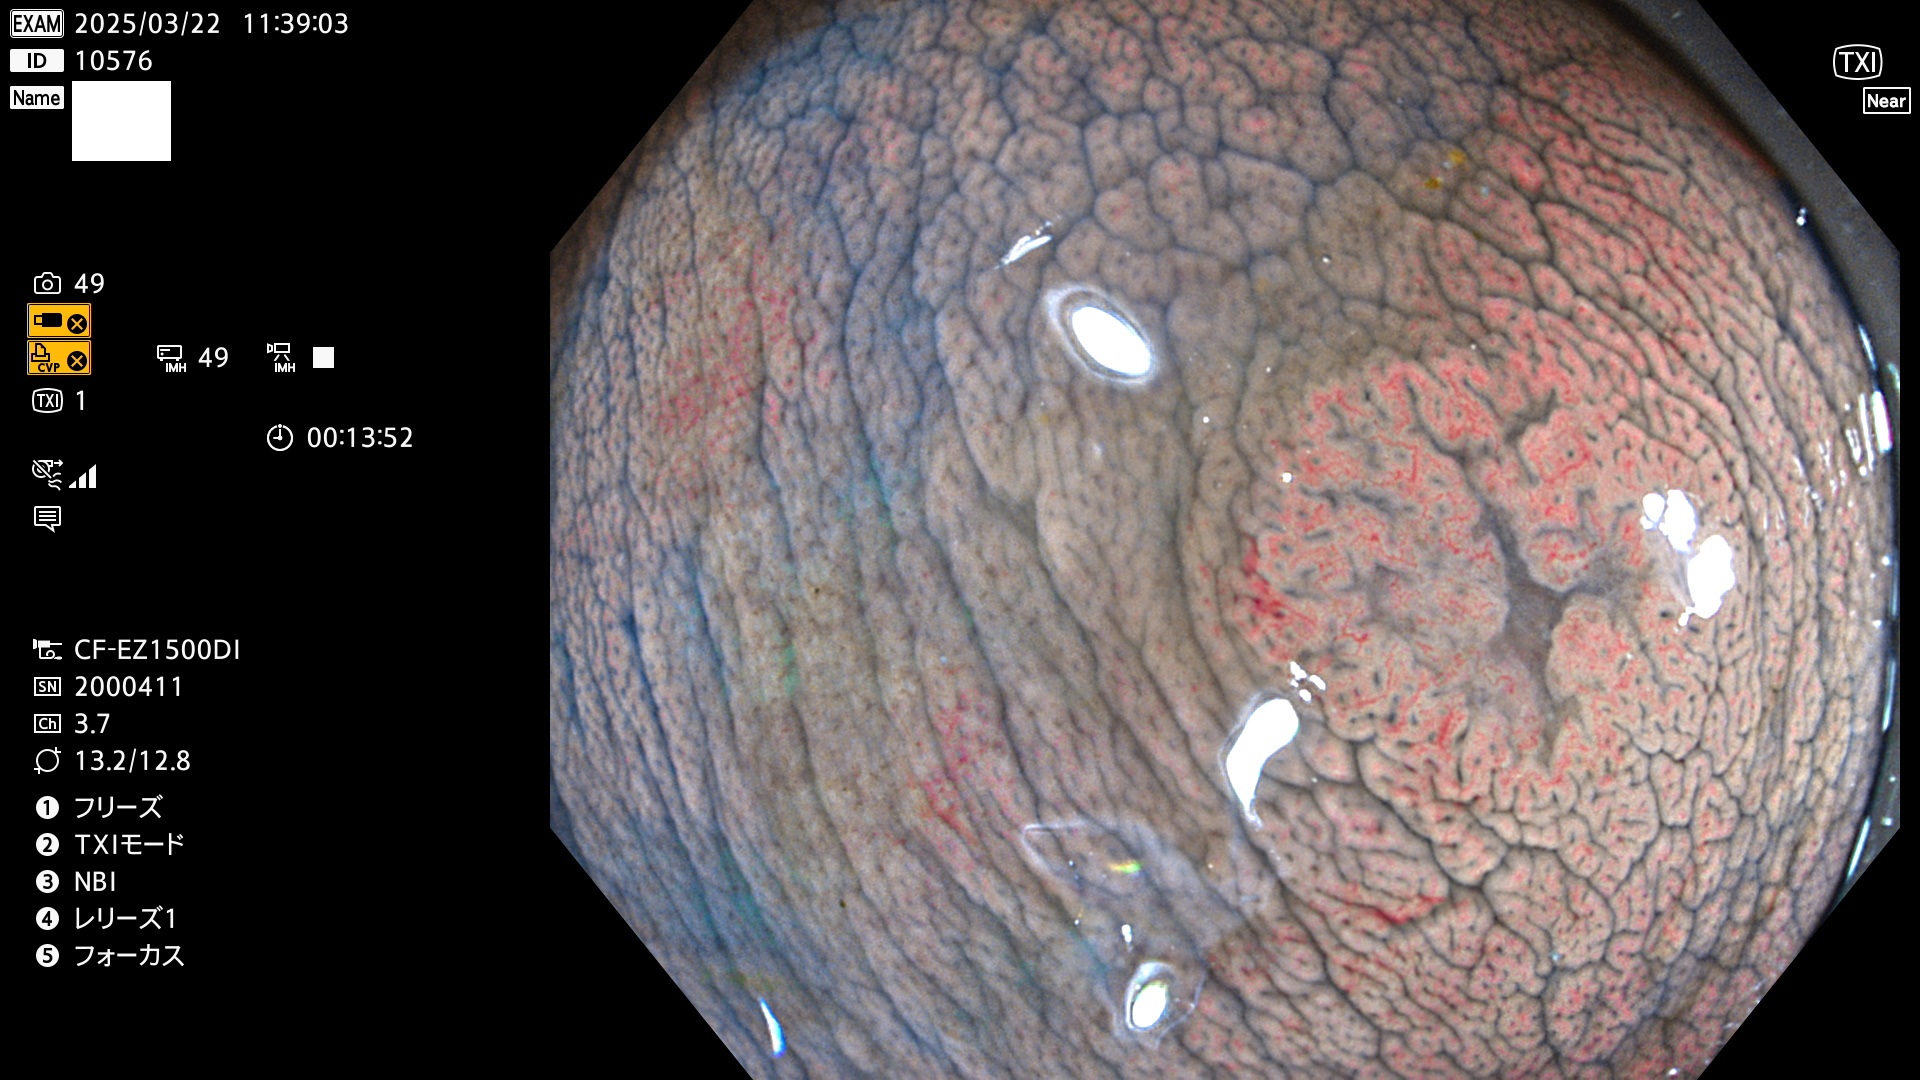

今週のUb、Uc型腺腫

完全に平坦な物をUb、陥凹している物をUcと呼びます。Ubは認識が困難で、Ucはびらん(炎症)と紛らわしいために見落とされやすく、「内視鏡後・大腸癌」の原因になります。

抽出の対象期間 2025年3月20日〜3月23日の4日間(48件の検査)10個 (10/48=21%)